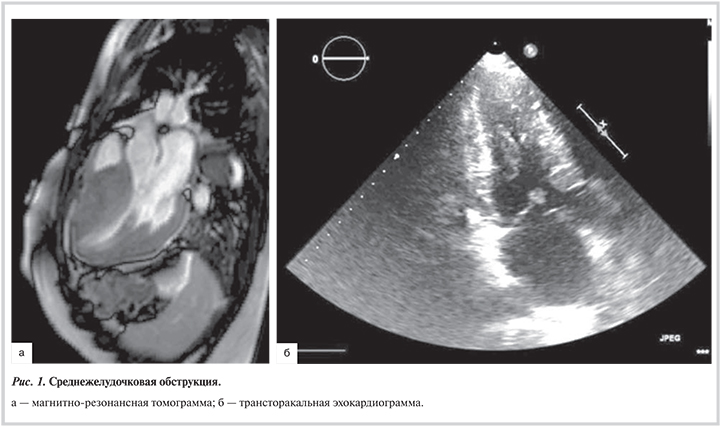

С целью оценки внутрисердечной анатомии всем обследуемым на до- и послеоперационнном этапе выполняли контрастную магнитно-резонансную томографию и чреспищеводную эхокардиографию (ЭхоКГ) (табл. 2, рис. 1).